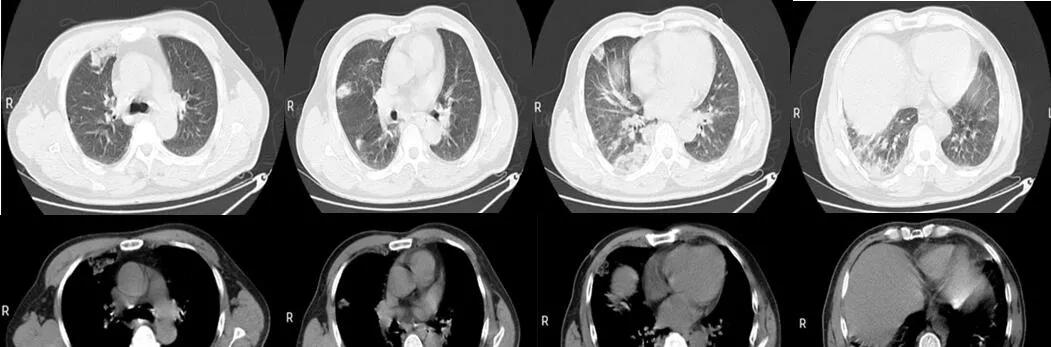

(三)胸部CT:双肺感染性病变,双肺多发高密度片状影(图一所示)。

入院时胸部CT(图一)